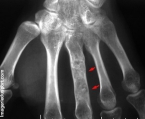

* fracture pathologique

- risque de récidive en cas de curetage incomplet au niveau des os des mains